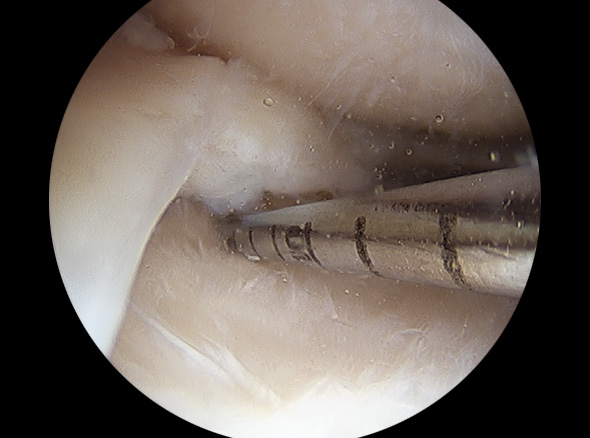

약 7mm 정도의 2~3개의 작은 구멍을 무릎 관절 주변에 뚫고

초소형 카메라가 달린 내시경을 삽입한 후 내부를 확인하며

손상된 반월상 연골판을 다듬어줍니다.